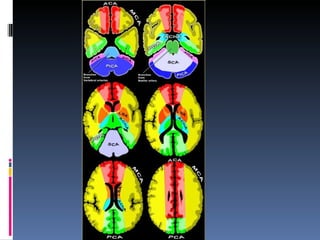

Vraag 107 De thalamus wordt gevasculariseerd door de arteria cerebri media Onjuist

Rood: medial lenticulostriate arteries, branches of A1  ( anterior inferior parts of the basal nuclei and the anterior limb of the internal capsule)

Oranje: lateral lenticulostriate arteries, branches of M1 (superior part of the head and the body of the caudate nucleus, most of the globus pallidus and putamen and the posterior limb of the internal capsule.

Groen: Posterior thalamoperforating arteries branch off the P1 segment and supply blood to the midbrain and thalamus.